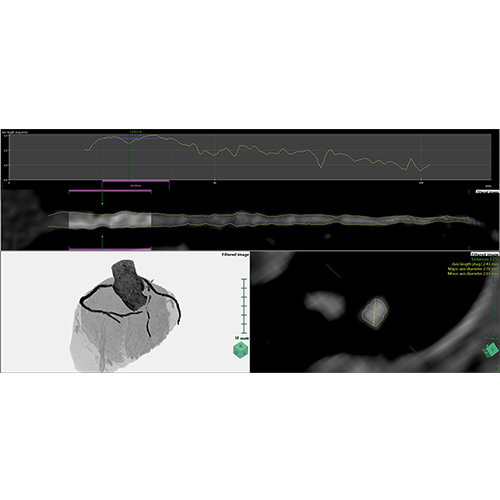

ANYTHINK 经导管主动脉瓣膜置换术分析系统